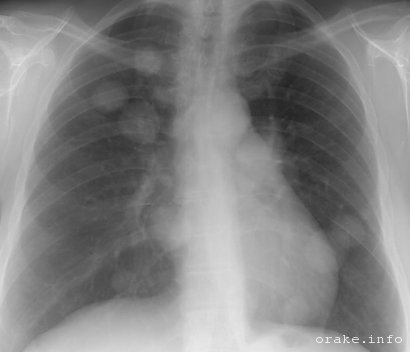

Метастазы в легких часто протекают бессимптомно, их обнаружение осуществляется случайно во время рентгенографического исследования грудной клетки.

- Рентгенография бронхо-легочной системы, которая может обнаружить одиночные или множественные метастатические узлы в легочной системе.